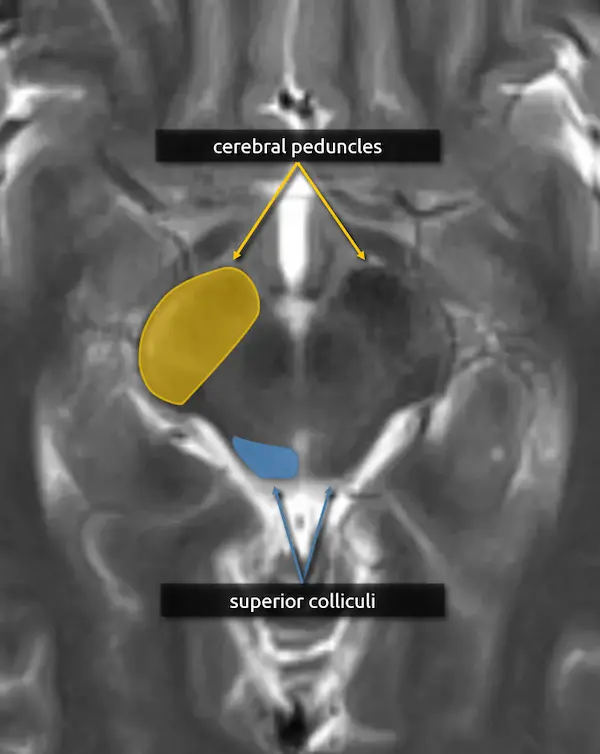

1. Cerebral peduncles:

The cerebral peduncles are located in the ventral midbrain and connect the midbrain to the cerebrum. They contain large named white matter tracts that are important for motor function, for example:

a. Corticospinal tract (limbs and trunk)

b. Corticobulbar tract (face and neck)

c. Corticopontocerebellar tract (coordination)

The individual tracts are not well visualized on routine imaging, but the corticospinal tract is the largest and is roughly in the center of the peduncle; see level 5 for more detail.

Mass effect of the cerebral peduncle is an important sign of uncal herniation.

2. Superior colliculi:

The superior colliculi are located in the caudal midbrain along the dorsal aspect, forming two of the four bumps on the surface. They are important for coordinating eye movements towards motion and visual stimuli. There are white matter tracts connecting the superior colliculi to areas crucial for coordinated motor function, such as the basal ganglia and substantia nigra (see level 3).

Atrophy of the superior colliculi in progressive supranuclear palsy contributes to the characteristic vertical gaze palsy.